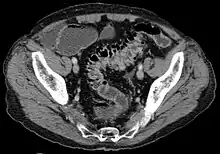

Diverticula typically occur in the sigmoid colon, which is commonplace for increased pressure. The left side of the colon is more commonly affected in the United States while the right side is more commonly affected in Asia.[4] Diagnosis is often during routine colonoscopy or as an incidental finding during CT scan.[2]

- Contrast CT is the investigation of choice in acute episodes of diverticulitis and where complications exist.